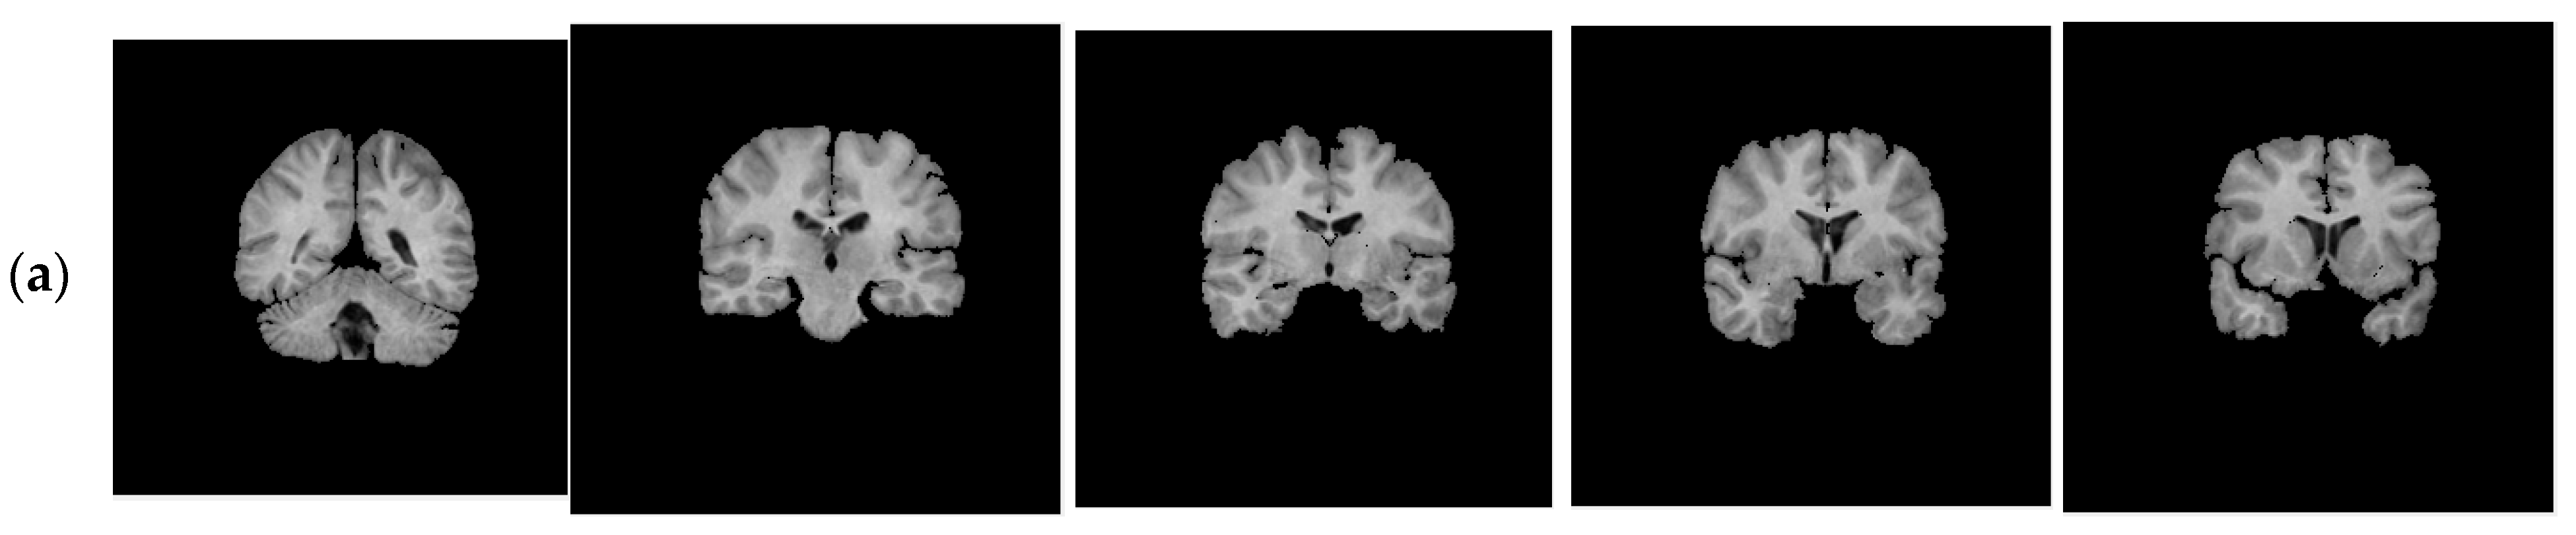

With regard to the T1-weighted MRI brain datasets, the performance of the HMRF-WOA was evaluated for 20 normal subjects. Figure 18 shows some slices of one subject (slices 20, 28, 32, 35, and 39); Figure 18a presents the initial slices images, (b) represents the ground truth segmentation, and (c) shows the HMRF-WOA segmentation results.

Moreover, Figure 18 illustrates the segmentation results of the proposed algorithm using MR brain images from the IBSR database. Figure 18a presents the slices of the original brain image; Figure 18b is the ground truth slice images; and Figure 18c shows the segmented brain MR images using the HMRF-WOA approach on the sample image of one subject. GM is shown in yellow, WM in red, CSF in green, and the background in blue.

Figure 18. Segmentation results of IBSR dataset: (a)—initial images; (b)—ground truth images; (c)—segmentation results.